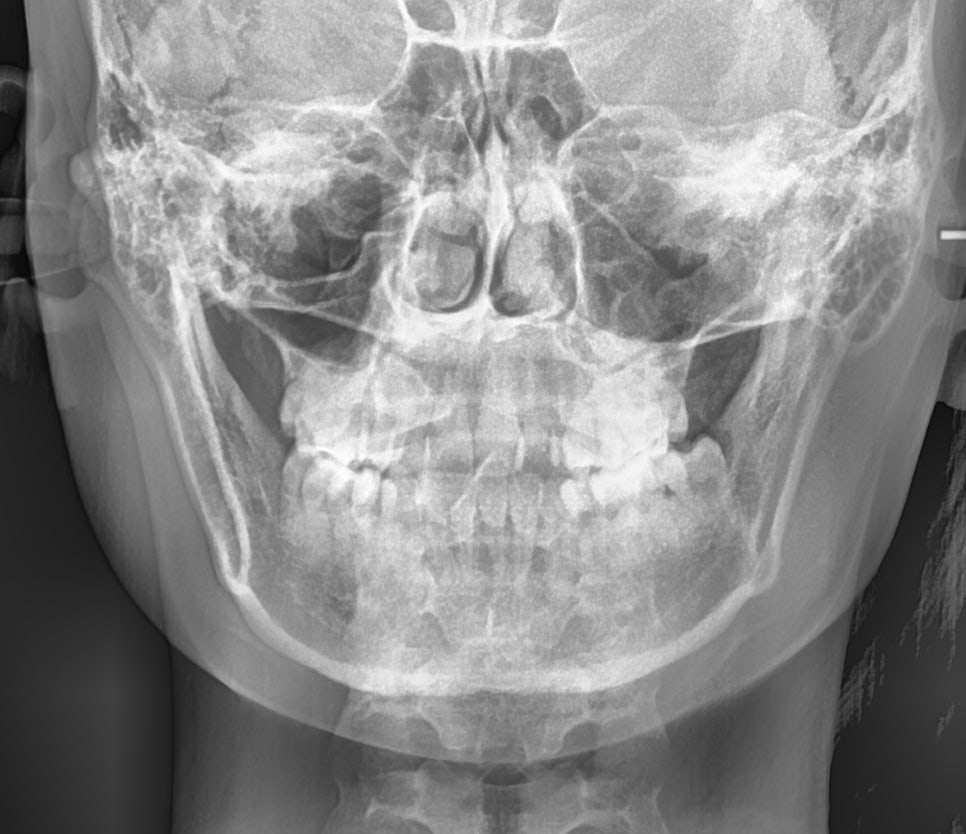

그로 인해,

코 끝과 턱끝을 이은 선이

입술이 후퇴되어 있습니다.

이러한 형태를

골격성 3급 부정교합 이라 하는데요.

이는 아래턱이 위턱보다

더 앞으로 자라 있는 상태로

정상 교합에서는 윗니가 아랫니를

자연스럽게 덮고 있어야 되지만,

이러한 문제가 있을 경우

아랫니가 윗니보다 앞으로 나와 있거나

위아랫니가 절단 및 반대 교합으로

맞물리게 됩니다.

얼굴 좌우 비대칭이 거의 없고,

턱 끝 위치도 중심에 가깝고

교합기능도 안정적이었습니다.